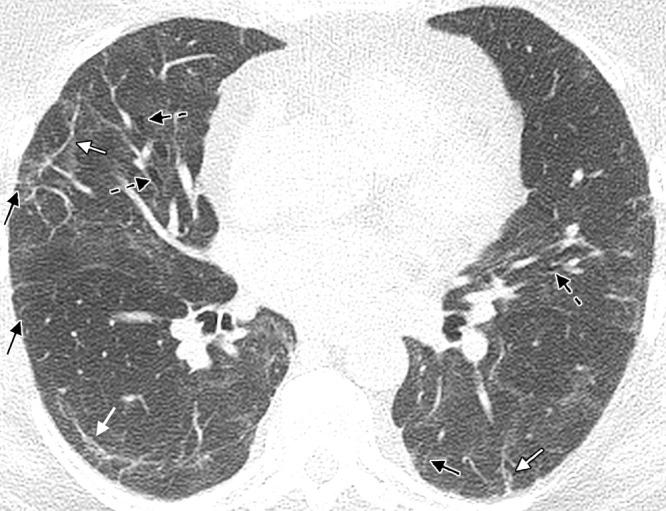

This case presents a patient with severe COVID-19 pneumonia requiring intensive care unit admission and a prolonged hospital stay. The infection resulted in long-term morbidity, functional decline, and abnormal chest CT findings. The mechanisms for long-term lung injury after COVID-19 infection, imaging appearances, and the role of imaging in follow-up are discussed.

本病例报告了一位患有严重 COVID-19 肺炎的患者,需要入住重症监护病房和长时间住院治疗。该感染导致长期发病、功能下降和异常的胸部 CT 发现。讨论了 COVID-19 感染后长期肺损伤的机制、影像学表现以及影像学在随访中的作用。